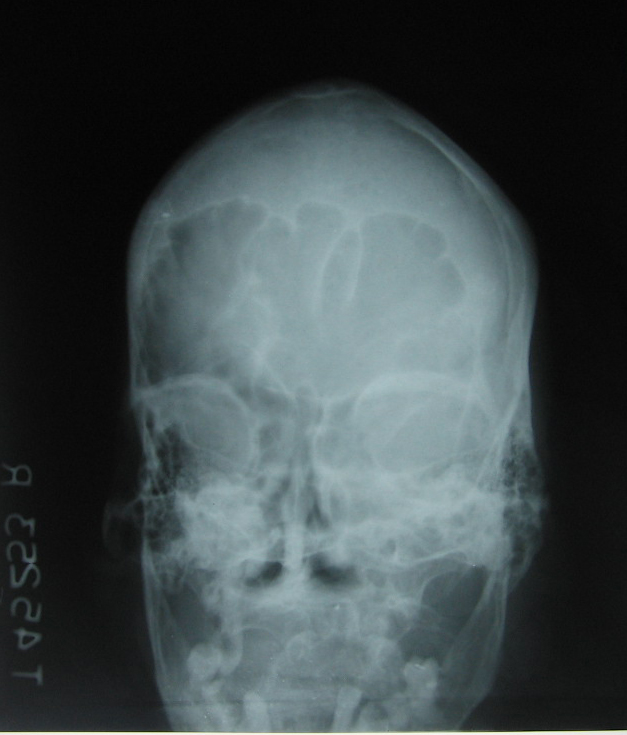

acromegaly 2 skull A P